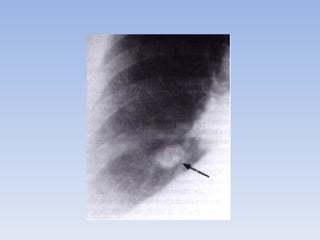

Infiltrado precoz tuberculoso

• Esta forma de tuberculosis es la más frecuente

en el adulto. La imagen del infiltrado precoz

suele ser de 3-10 cm de diámetro, tiene unos

límites imprecisos y borrosos y su localización

preferentemente es a nivel subclavicular.

Se trata de una lesión intensamente

inflamatoria con necrosis caseosa

central.

Infiltrado precoz tuberculoso •Esta forma de tuberculosis es la más frecuente en el adulto. La imagen del infiltrado precoz suele ser de 3-10 cm de diámetro, tiene unos límites imprecisos y borrosos y su localización preferentemente es a nivel subclavicular.

Se trata deuna lesión intensamente inflamatoria con necrosis caseosa central.